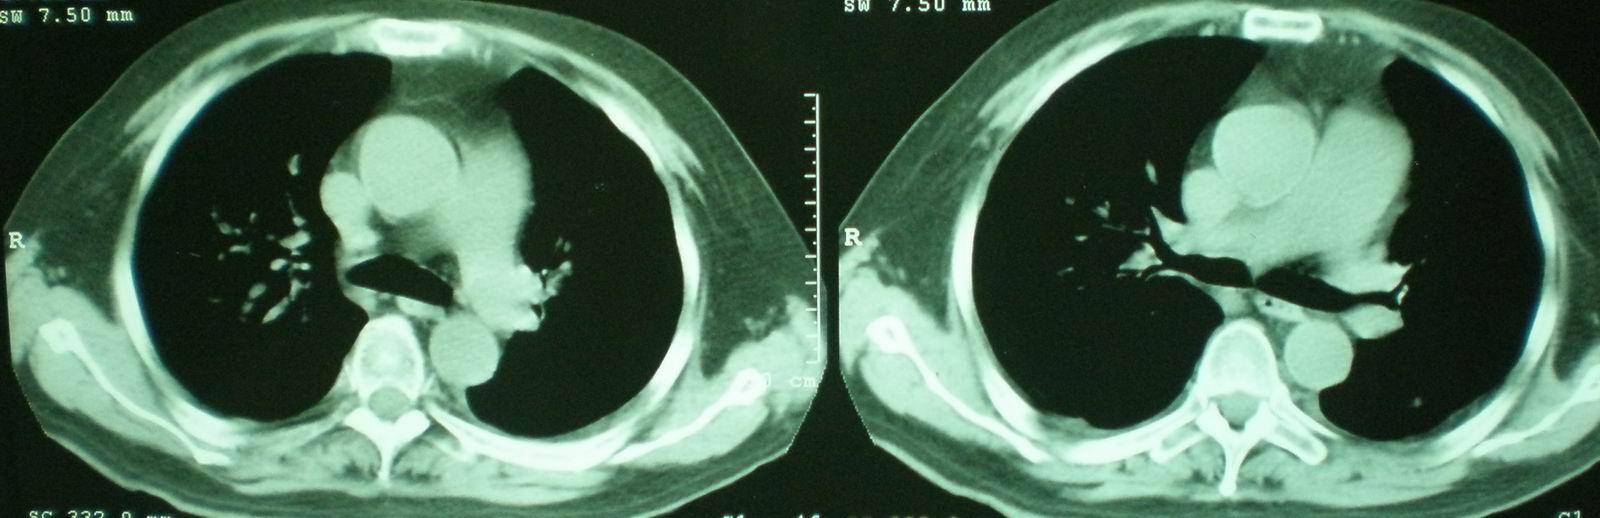

2008年9月8日ct片: